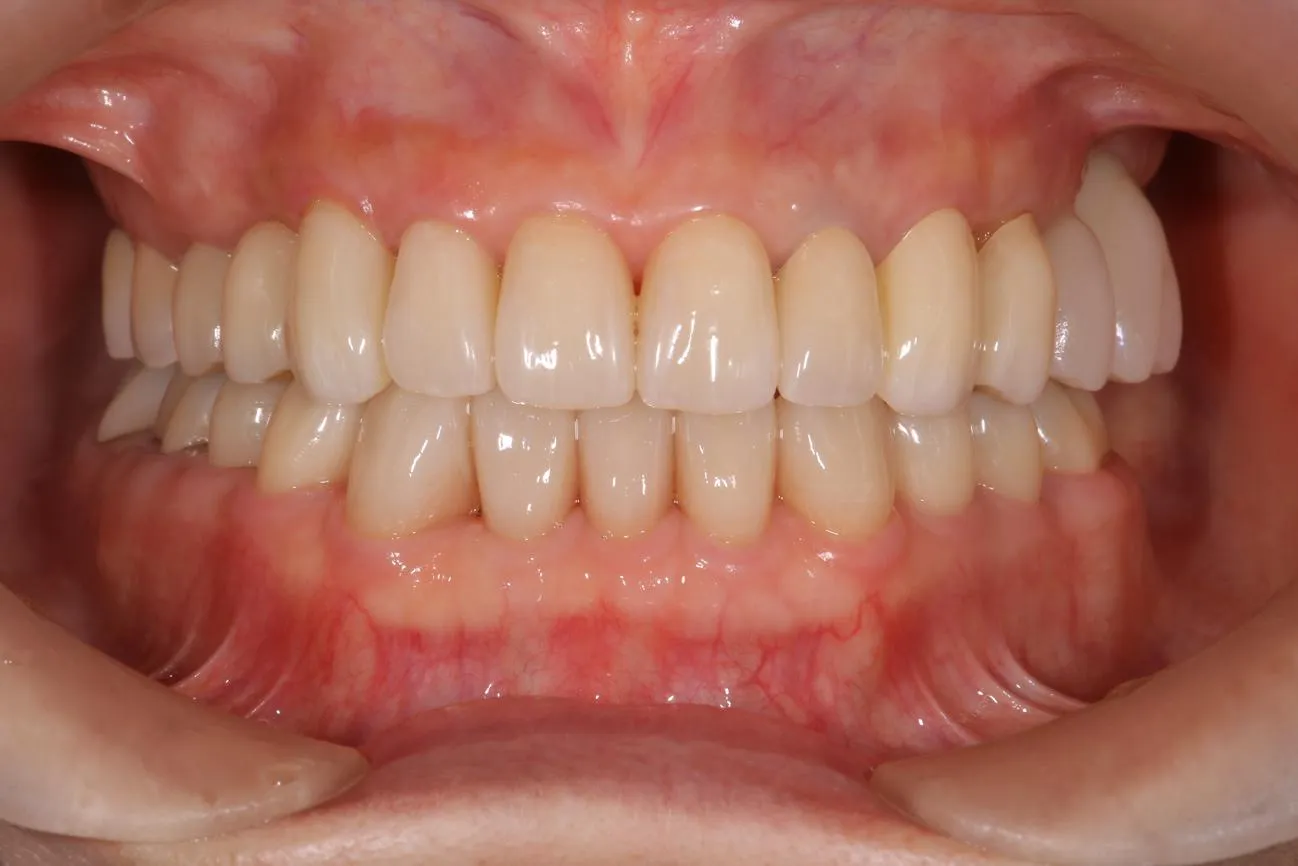

治療後